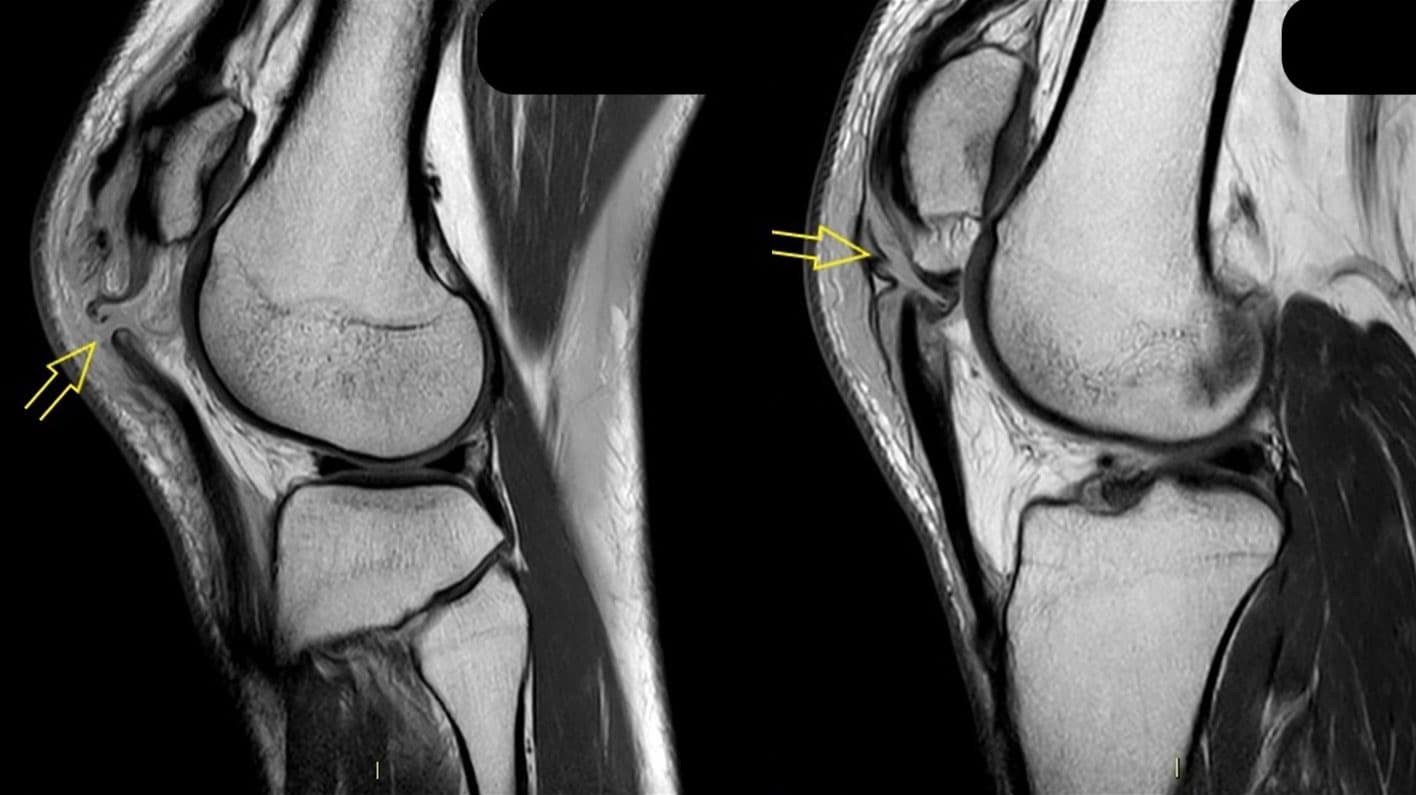

Patienten fik foretaget MR-skanning, som bekræftede PSR og viste påfaldende ens læsioner i anteriore ledkapsel på begge knæ, men ingen andre intraartikulære læsioner (Figur 1). Patienten gennemgik operation af begge knæ på tredjedagen, hvor patellasenen blev sutureret med nonresorberbar sutur ad modum Krakow igennem vertikale borehuller i patella samt metalcerclage fra tuberositas tibiae og omkring patella. Denne metode har vist den laveste risiko for svigt [4], men medfører ofte en sekundær operation med fjernelse af cerclager, hvis de generer, eller ved risiko for, at de knækker. Patienten fik fjernet cerclager fra begge knæ efter ca. fem måneder (Figur 1).

Denne case bidrager til opmærksomhed omkring skader på knæets ekstensorapparat og den diagnostiske tankegang. Patienten var formodentlig prædisponeret, idet han tidligere havde pådraget sig senerupturer ved forskellige skadetidspunkter [3]. I dette tilfælde var der ikke andre intraartikulære læsioner. I et nyligt, systematisk review fandt man 45 dokumenterede tilfælde af samtidig, bilateral PSR, hvoraf kun ti patienter fik foretaget præoperativ MR-skanning. I 18 ud af de 45 tilfælde skete skaden ved sportsaktivitet og i 20 tilfælde ved faldtraumer [2]. Det er altså en sjældenhed at pådrage sig bilateral PSR, og det har ikke været anset som standardpraksis at foretage MR-skanning i denne forbindelse. Turner et al viste, at præoperativ MR-skanning ved skader i ekstensorapparatet (quadriceps- og patellasenen) medførte øget diagnosticering af intraartikulære skader på 50,7%, hvoraf meniskskader var de hyppigste. Af alle ledsagende skader var kun 4,5% kirurgisk behandlingskrævende, men risikoen var højere ved PSR end ved andre ekstensorapparatskader [1]. I denne case var der læsion i anteriore ledkapsel på begge knæ. Selv om dette ikke i sig selv ændrede behandlingen, var det af betydning for operationsplanlægningen at kende til sekundære skader. Med tanke på, at de fleste kan returnere til samme sportsgren, som skaden er sket ved [5], synes det meningsfuldt, at MR-skanning overvejes ved mistanke om PSR.